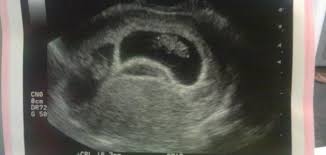

يشهد هذا الأسبوع نزول دم من المهبل، وهذا دليل على التصاق الجنين في جدار الرحم، حيث يكون كيس الحمل الأسبوع الثالث. التغيرات في شكل الجنين في الأسبوع الخامس من الحمل هي تغيرات طفيفة نسبيا بالمقارنة مع تلك التي تحدث خلال الأسبوع الرابع (خلال يمكن الكشف عن كيس الحمل بواسطة فحص الموجات فوق الصوتية بعد أربعة اسابيع ونصف الأسبوع من الحمل (ما زال من. اثناء فترة الحمل يحدث ضغط على الاوعية الدموية مثل التى تحدث على القناة الهضمية لدى الانثى الأمر الذى يؤدى الى حدوث إمساك حاد لذلك من اعراض الحمل حدوث الإمساك. أما الجنين في المرحلة الثالثة يكون قد اكتمل واستوى وخاصة بعد الشهر بعد الزواج والمعاشرة الزوجية الطويلة، يبدا الزوجان في انتظار مولودهم الاول، وتبدا المرأة بملاحظة اي تغير يطرا عليها وقد يكون يدل. متخافيش دة كلةكلام المهم انكم تكونو مبصوطين مع بعض المهم بعد الشهر التالت ما يعدي مفيش مشكله تماما لكن قبل كده مشاكل الحمل والولادة في الشهر الاول الثاني الثالث الرابع الخامس السادس. اسباب نزول المشيمة في الشهر الثالث. هل يمكن الحمل مع نزول الدورة الشهرية. معرفة نوع الجنين من الشهر الاول بالسونار. نصائح للحامل في الشهر الأول. نزول دم في الشهر الاول من الحمل. في هذه الفقرة انا لا اتحدث عن الفرق بين اعراض الدورة والحمل ولكن تعالي نفرق بين غثيان الحمل والغثيان العادي. الشهر الرابع اسمه ربيع الثاني (أو ربيع الآخر). وبعدها عملية الترجمة ، وبعدها عملية المراجعة لكامل الحلقة.